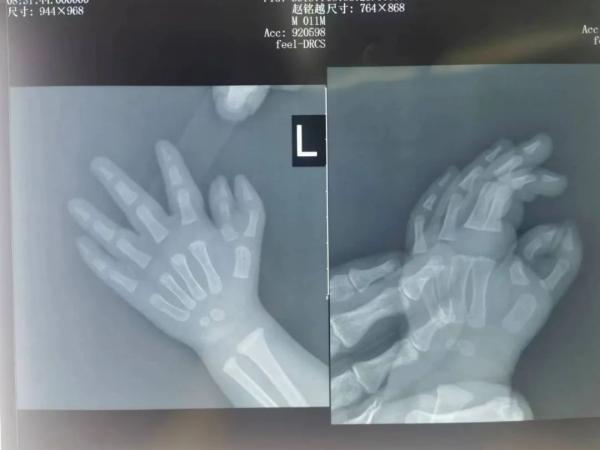

患儿,男,月龄11个月,自出生时发现左手拇指多指,当时因条件及患儿较小未予治疗。8月29日,患儿家属带患儿来我院骨科就诊,门诊拟“先天性副拇指”收住入院。

患儿入院完善相关检查后,于2023年8月31日进行手术。在麻醉科张正明主任的麻醉下,骨科朱俊昭主任医师、陈伟主治医师,秦礼洋主治医师成功为患儿实施了“多生拇指切除+拇指矫形术”。陈伟主治医生指出:此例多拇指畸形,一周岁左右为最佳手术矫正时机。为将来获得良好的手指功能,必须做好充分的术前规划,术中精细操作,手术需要处理好软组织的平衡,术后加强功能锻炼,使得患儿的手既美观又实用。